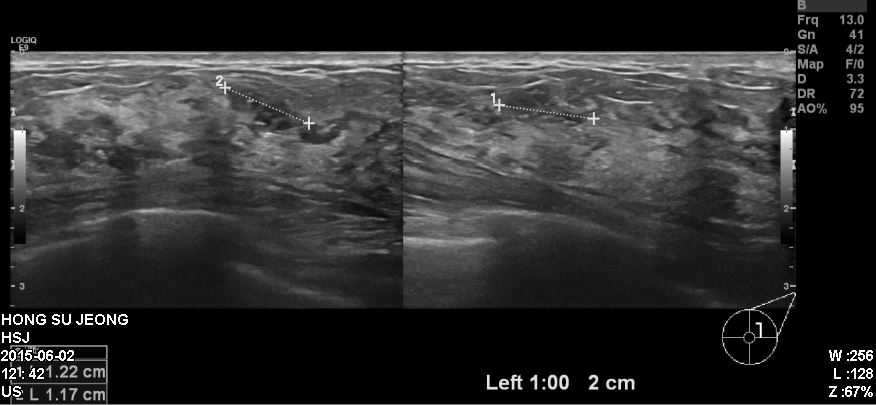

건진상 이상소견으로 내원하신 40대환자분이십니다.

이전부터 만져지는 혹이있었고 이번 국가검진을 통해 발견되어

본원에서 타원 유방초음파상 확인되는 좌측1시방향에 혹을 조직검사 시행하였고

침윤성유관암으로 진단되었습니다.